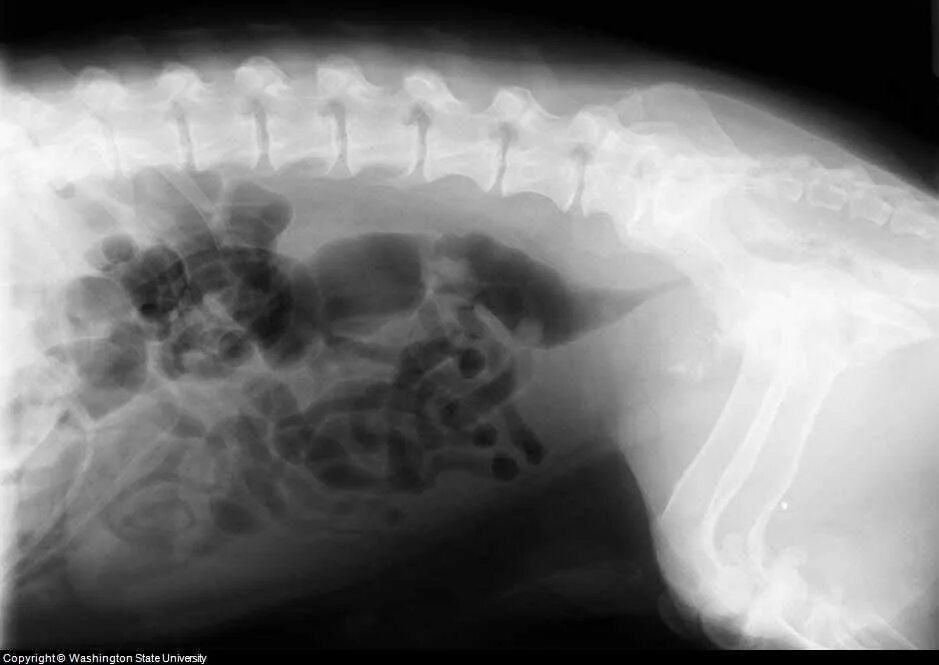

Лимфома у собак симптомы